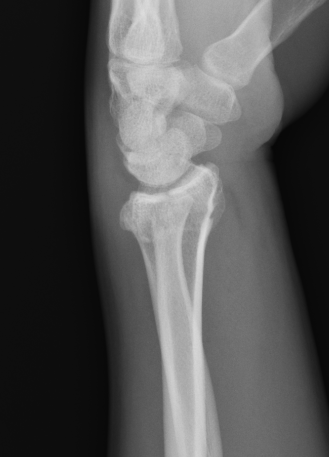

Distal radius fracture with shortening and dorsal tilt

Articular incongruency > 2 mm

Sigmoid notch disruption and DRUJ instability